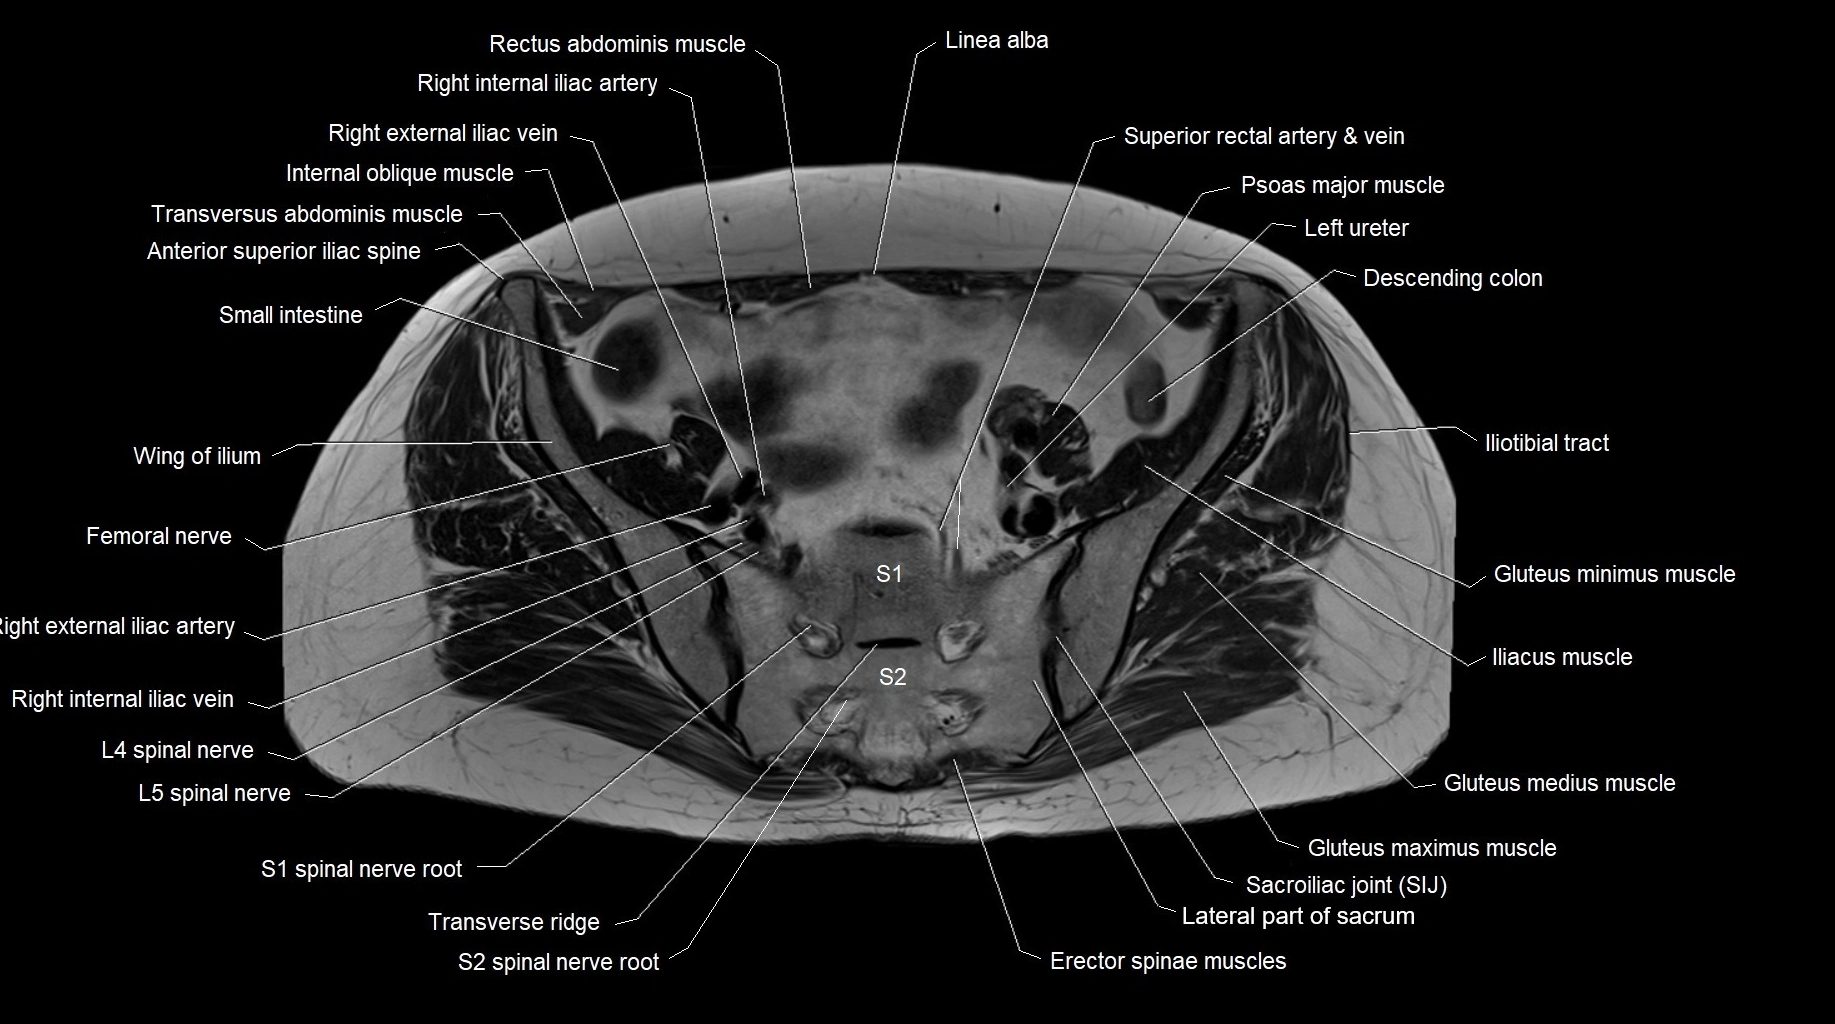

- Anterior superior iliac spine

- Erector spinae muscles

- Femoral nerve

- Iliopsoas muscle

- Iliotibial tract

- Psoas major muscle

- Sacroiliac joint